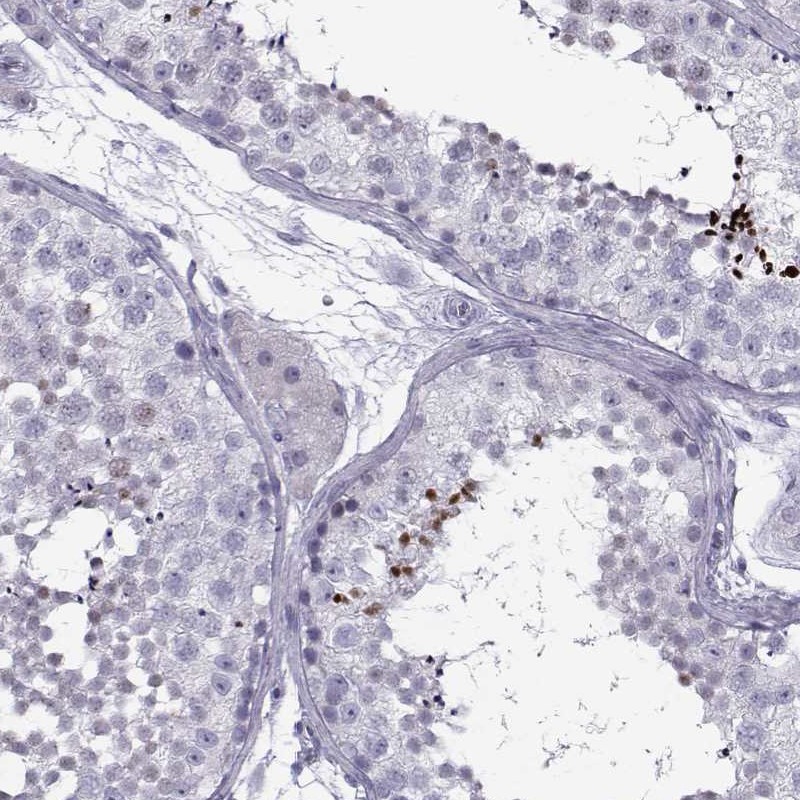

Immunohistochemical staining of human testis shows strong nuclear positivity in cells in seminiferous ducts.